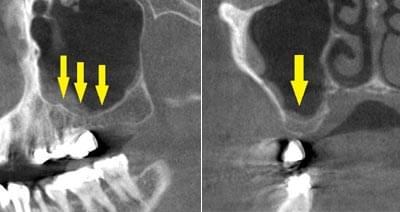

写真のように、CTで見ると、骨吸収の様子が良く分かり、下顎骨の中を通る神経近くまで骨がありませんでした。

さらに、CTで、別な方向から見ると、黄色矢印のように骨が吸収されていて、緑色矢印で示される神経の通る管に迫り、インプラントが埋入できるような骨量はありませんでした。